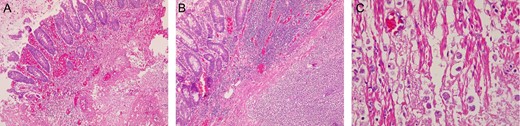

Histopathological examination of the resected bowel revealed, multiples ulcers in the colonic wall along with necrosis and perforation in most of them. The ulcers were covered with an inflammatory exudate and necrotic material (Fig. 3A). Trophozoites of E. histolytica were found within the ulcers and many of them invaded the colonic wall causing a severe inflammatory reaction (Fig. 3B and C).

(A) Colonic ulcer, with inflammatory reaction, and hemorrhage. (B) Severe inflammatory reaction on the bowel wall. (C) Trophozoites of Entamoeba histolytica invading the colonic wall.